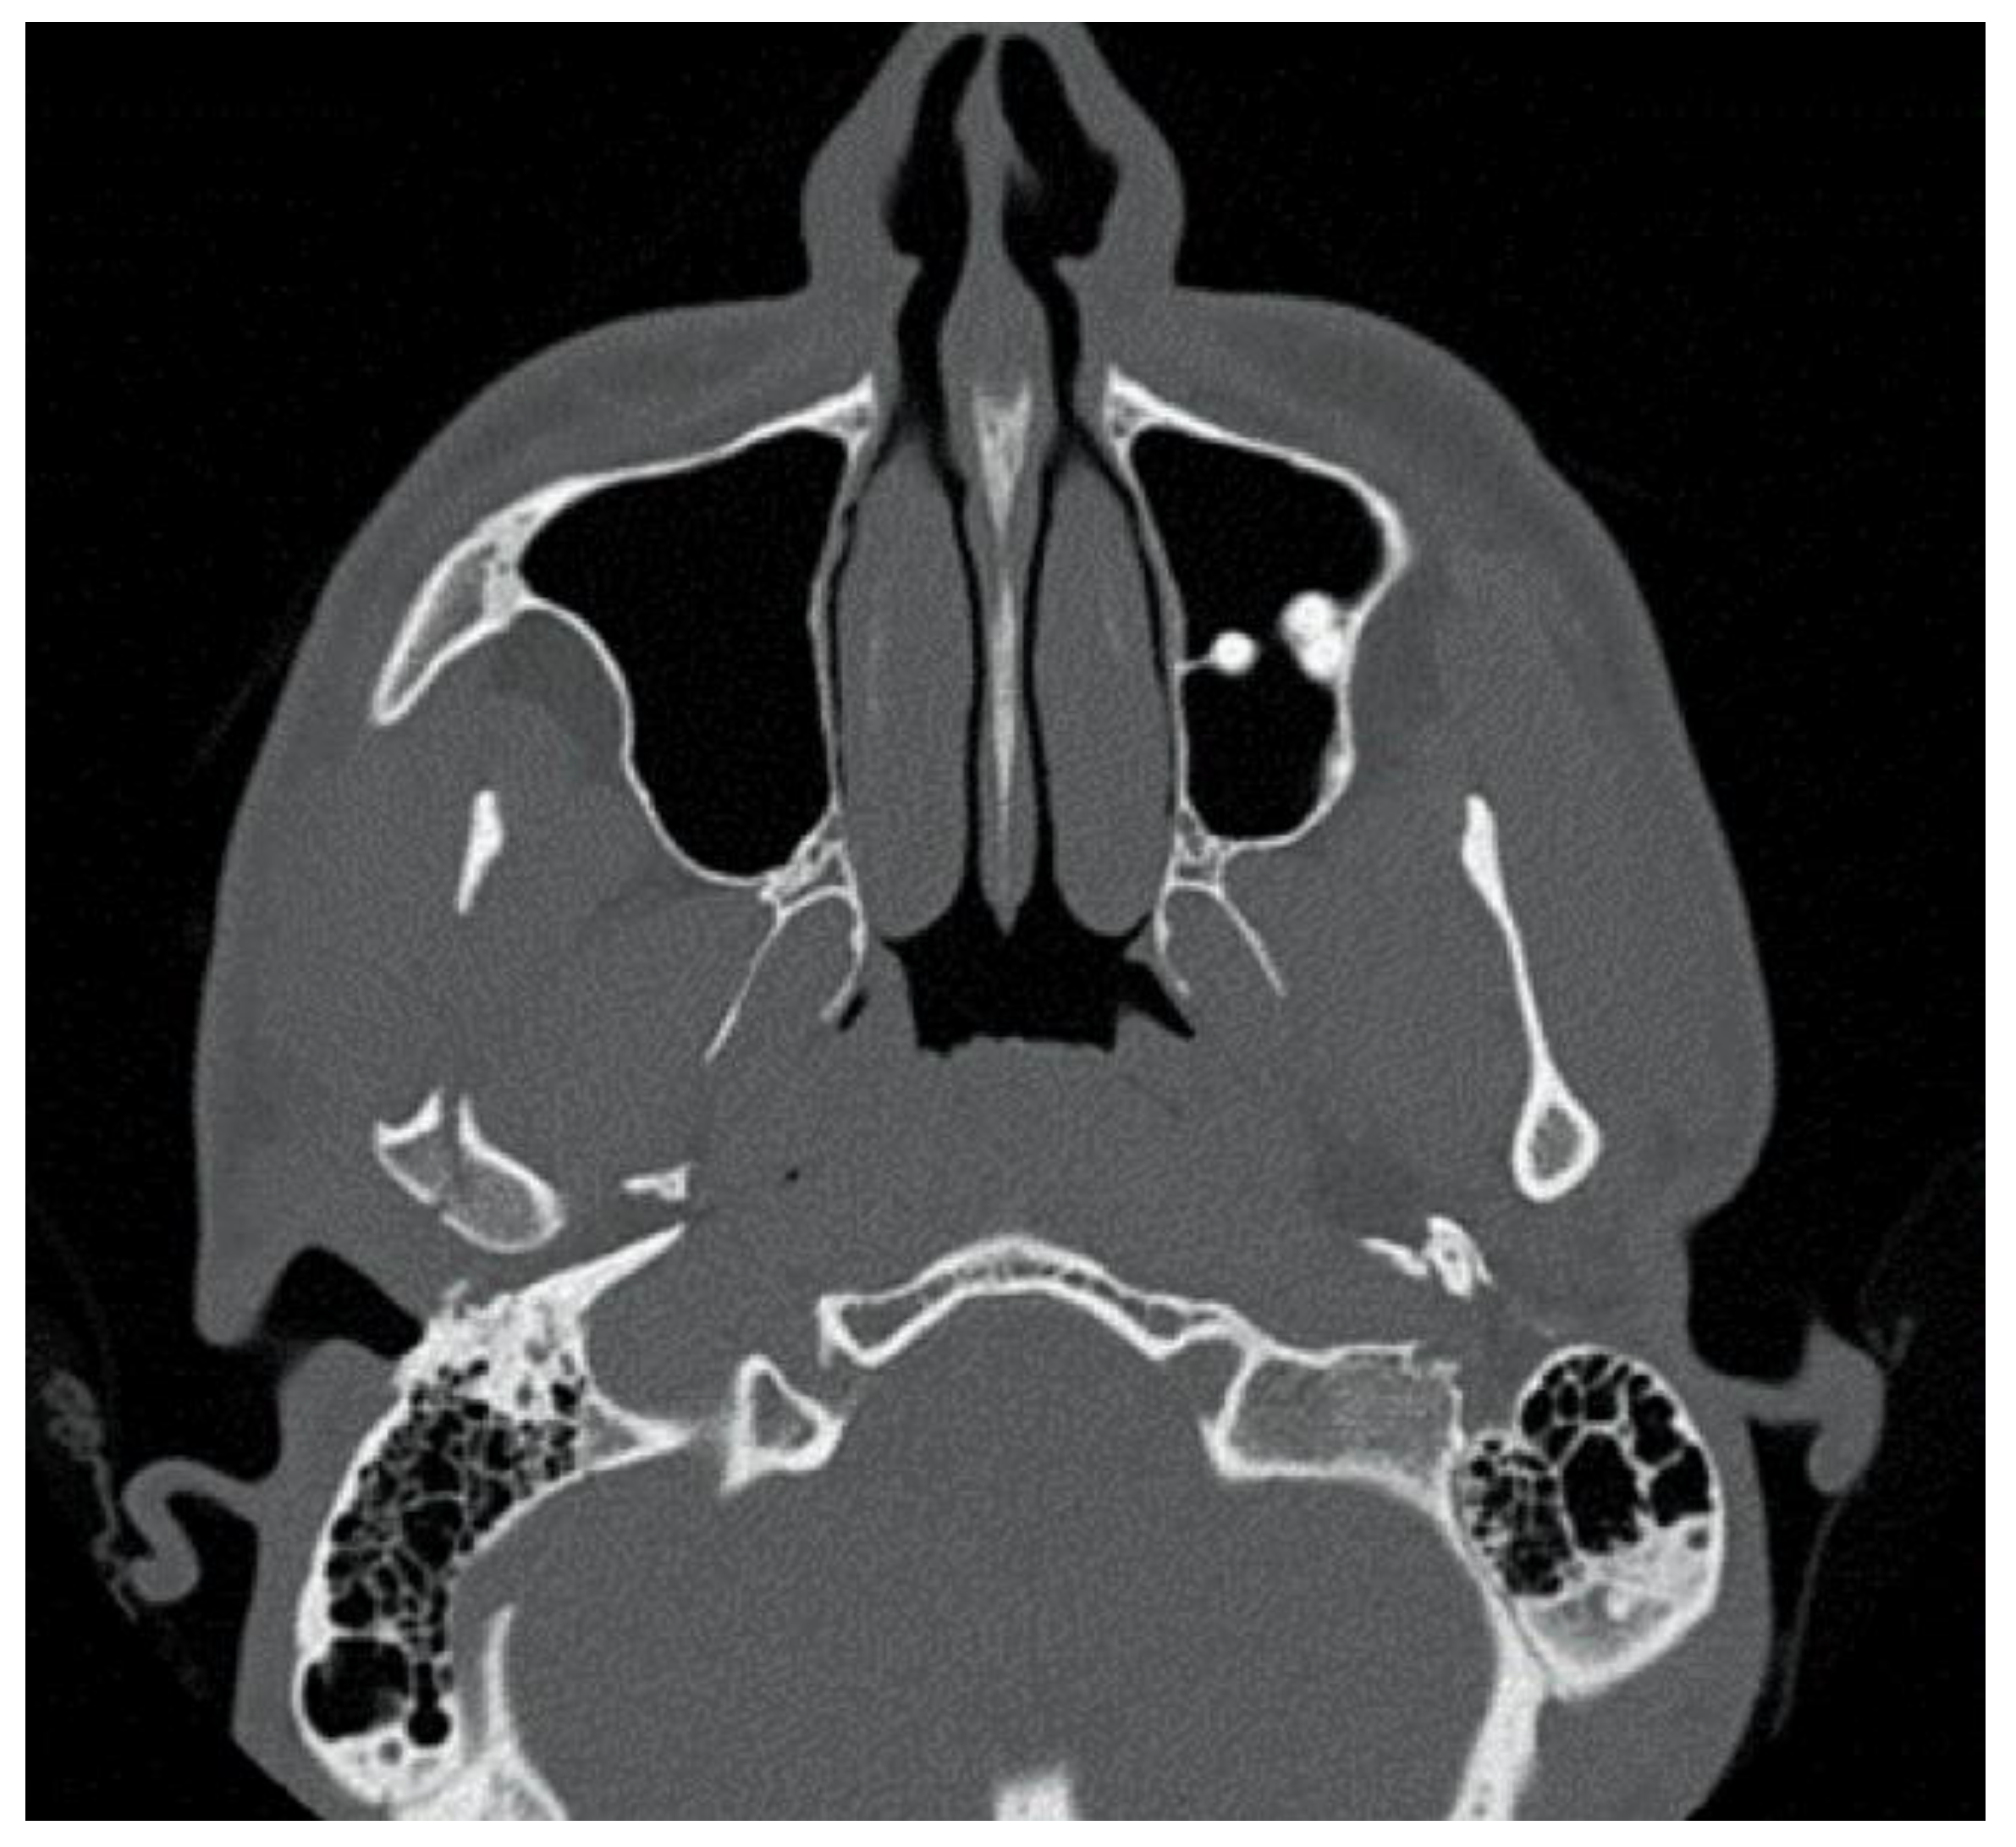

The second patient was a male, aged 20, with a right condylar diacapitular fracture (Figure 4). The patient also presented a coronal fracture of the element 43 due to the trauma. The other teeth were sound, but the 37 was unerupted. He presented a slight class III malocclusion and a posterior open bite on the left. In this case, there was the need to not exert force on the fractured tooth, and to balance the traction points of the rubber bands despite the absence of the 37, avoiding extrusive forces on the 27.

Figure 4. Patient 2, male, aged 20, with a right condylar diacapitular fracture.